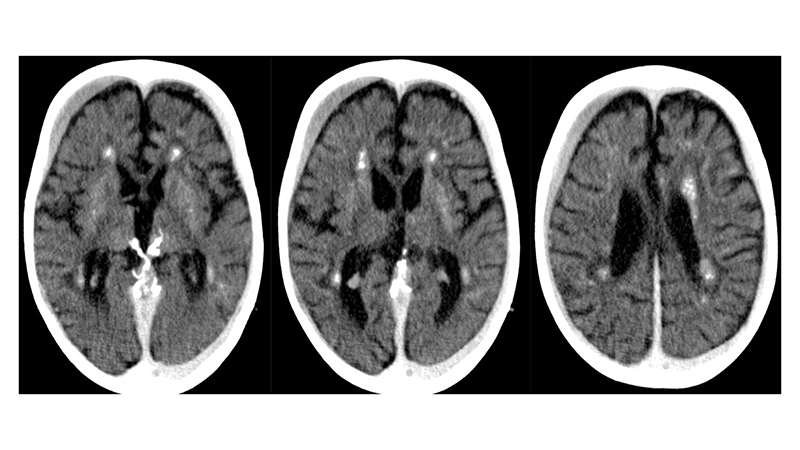

- Στην μαγνητική τομογραφία βλέπουμε μικροισχαιμικές αλλοιώσεις στο εγκεφαλικό στέλεχος και υποεπενδυματικά,

- και υποσκληρίδια αιματώματα αμφοτερόπλευρα, κυρίως δεξιά.

- Πρόσφατη μαγνητική τομογραφία δείχνει αναστροφή των ισχαιμικών αλλοιώσεων του εγκεφαλικού στελέχους, αποκατάσταση του κοιλιακού συστήματος με ήπια υποεπενδυματική και φοιώδη ατροφία και πλήρη εξάλειψη των υποσκληριδίων συλλογών.